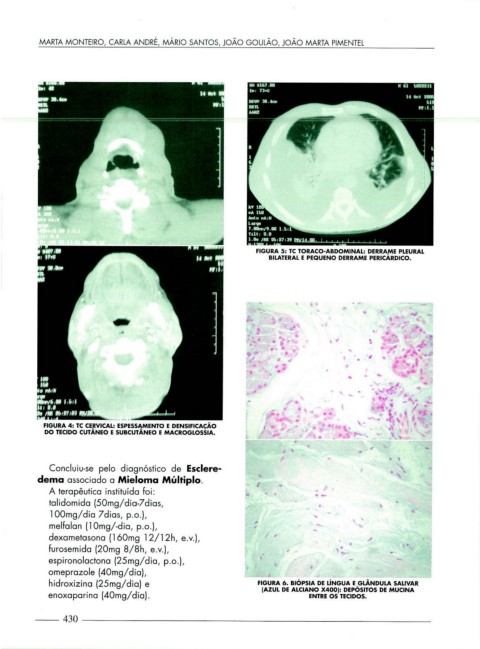

FIGURA 5: TC TORACO-ABDOMINAL: DERRAME PLEURAL

BILATERAL E PEQUENO DERRAME PERICÁRDICO.

FIGURA 4: TC CE.ftVICAL: ESPESS~MENTO E DENSIFICAÇÃO

DO TECIDO CUTANEO E SUBCUTANEO E MACROGLOSSIA.